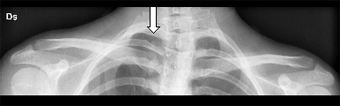

Viene eseguita una Radiografia (Figura 3) della clavicola che non dimostra alterazioni morfostrutturali a carico della stessa ma che mette in evidenza un'alterazione della morfologia delle prime due coste dello stesso lato, suggerendo l'ipotesi di fusione. Si decide pertanto il completamento diagnostico mediante l'esecuzione di una TAC a livello della gabbia toracica superiore (Figura 4) per stabilire l'esatta definizione anatomica dell'anomalia congenita sospettata.